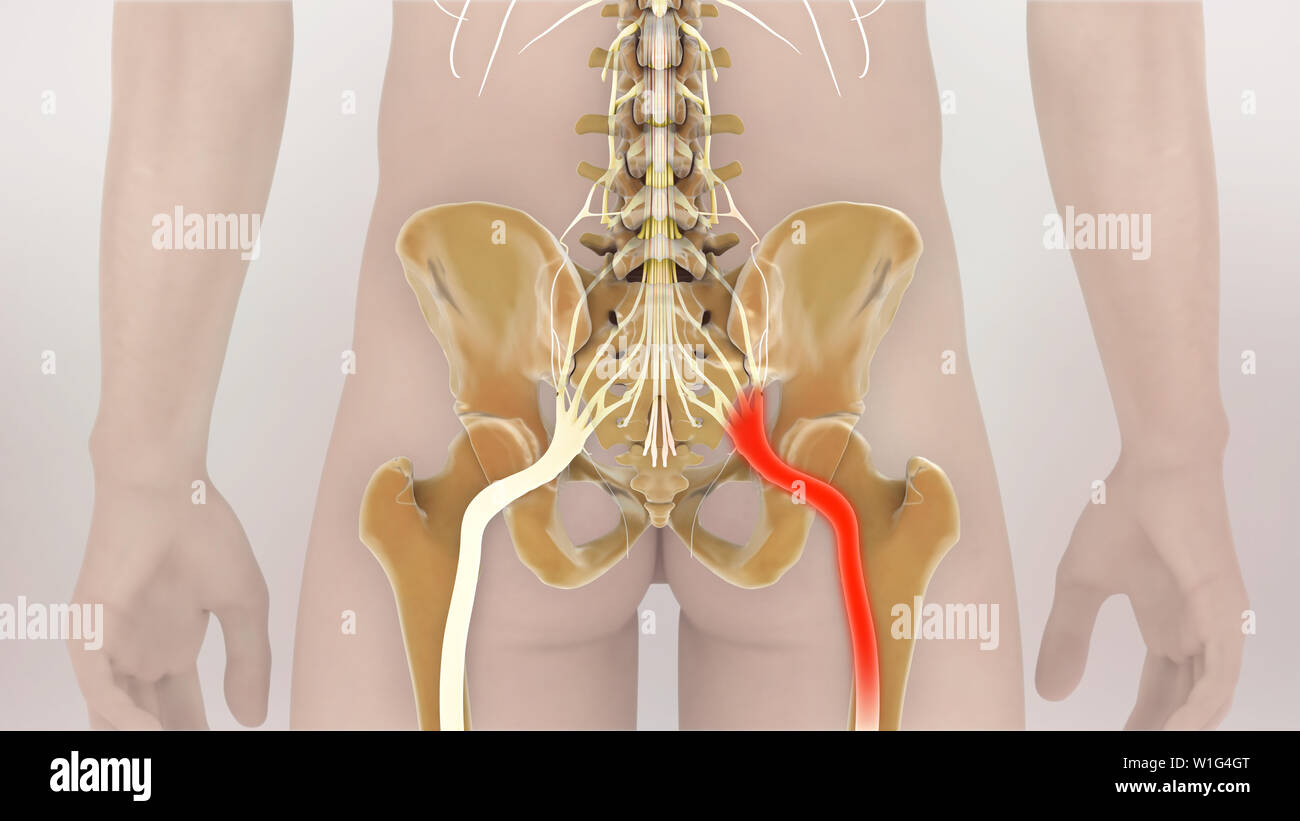

Nerf sciatique humain pincé, vision anatomique. illustration 3d. Banque D'Imageshttps://www.alamyimages.fr/image-license-details/?v=1https://www.alamyimages.fr/nerf-sciatique-humain-pince-vision-anatomique-illustration-3d-image364068055.html

Nerf sciatique humain pincé, vision anatomique. illustration 3d. Banque D'Imageshttps://www.alamyimages.fr/image-license-details/?v=1https://www.alamyimages.fr/nerf-sciatique-humain-pince-vision-anatomique-illustration-3d-image364068055.htmlRF2C48MEF–Nerf sciatique humain pincé, vision anatomique. illustration 3d.

Nerf sciatique humain pincé, vision anatomique. illustration 3d. Banque D'Imageshttps://www.alamyimages.fr/image-license-details/?v=1https://www.alamyimages.fr/nerf-sciatique-humain-pince-vision-anatomique-illustration-3d-image364067992.html

Nerf sciatique humain pincé, vision anatomique. illustration 3d. Banque D'Imageshttps://www.alamyimages.fr/image-license-details/?v=1https://www.alamyimages.fr/nerf-sciatique-humain-pince-vision-anatomique-illustration-3d-image364067992.htmlRF2C48MC8–Nerf sciatique humain pincé, vision anatomique. illustration 3d.

Nerf sciatique humain pincé, vision anatomique. illustration 3d. Banque D'Imageshttps://www.alamyimages.fr/image-license-details/?v=1https://www.alamyimages.fr/nerf-sciatique-humain-pince-vision-anatomique-illustration-3d-image364068117.html

Nerf sciatique humain pincé, vision anatomique. illustration 3d. Banque D'Imageshttps://www.alamyimages.fr/image-license-details/?v=1https://www.alamyimages.fr/nerf-sciatique-humain-pince-vision-anatomique-illustration-3d-image364068117.htmlRF2C48MGN–Nerf sciatique humain pincé, vision anatomique. illustration 3d.

Nerf sciatique humain pincé, vision anatomique. illustration 3d. Banque D'Imageshttps://www.alamyimages.fr/image-license-details/?v=1https://www.alamyimages.fr/nerf-sciatique-humain-pince-vision-anatomique-illustration-3d-image364068101.html

Nerf sciatique humain pincé, vision anatomique. illustration 3d. Banque D'Imageshttps://www.alamyimages.fr/image-license-details/?v=1https://www.alamyimages.fr/nerf-sciatique-humain-pince-vision-anatomique-illustration-3d-image364068101.htmlRF2C48MG5–Nerf sciatique humain pincé, vision anatomique. illustration 3d.

La douleur sciatique nerf pincé 3D Illustration Banque D'Imageshttps://www.alamyimages.fr/image-license-details/?v=1https://www.alamyimages.fr/la-douleur-sciatique-nerf-pince-3d-illustration-image259125016.html

La douleur sciatique nerf pincé 3D Illustration Banque D'Imageshttps://www.alamyimages.fr/image-license-details/?v=1https://www.alamyimages.fr/la-douleur-sciatique-nerf-pince-3d-illustration-image259125016.htmlRFW1G4GT–La douleur sciatique nerf pincé 3D Illustration

Nerf sciatique humain pincé, vision anatomique. illustration 3d. Banque D'Imageshttps://www.alamyimages.fr/image-license-details/?v=1https://www.alamyimages.fr/nerf-sciatique-humain-pince-vision-anatomique-illustration-3d-image364067990.html

Nerf sciatique humain pincé, vision anatomique. illustration 3d. Banque D'Imageshttps://www.alamyimages.fr/image-license-details/?v=1https://www.alamyimages.fr/nerf-sciatique-humain-pince-vision-anatomique-illustration-3d-image364067990.htmlRF2C48MC6–Nerf sciatique humain pincé, vision anatomique. illustration 3d.